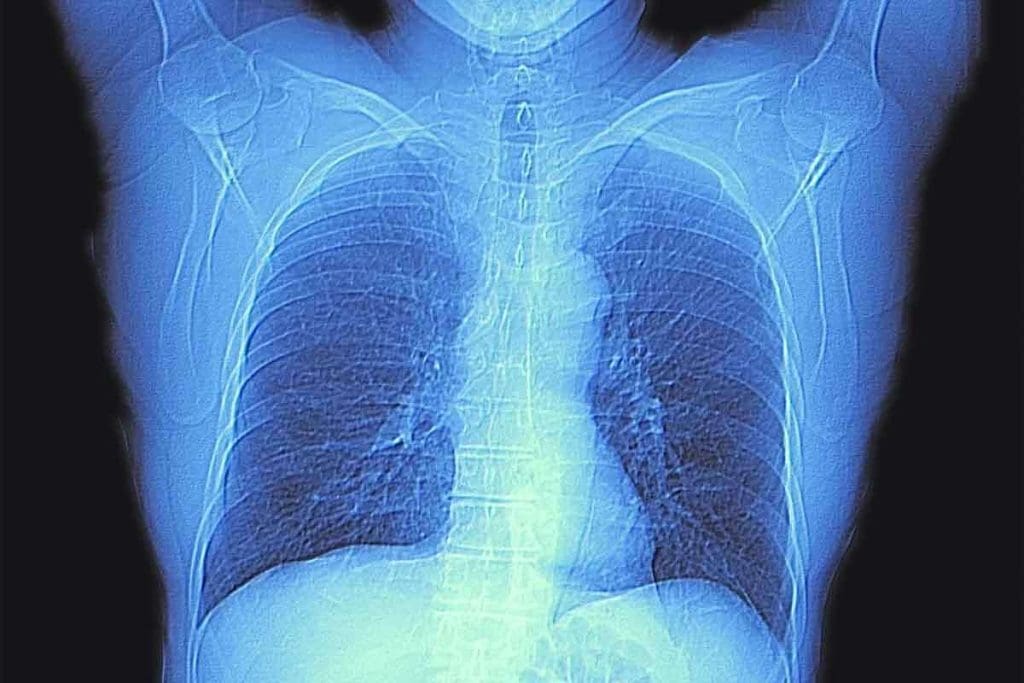

What Does a Chest CT Scan Show? A Detailed Overview

A chest CT scan gives doctors clear images of the chest area. They can see the lungs, heart, and esophagus in detail. This helps them find problems that other tests might miss.

These scans are great at spotting many health issues. A study on theNational Center for Biotechnology Information website shows how important CT scans are. They help doctors diagnose and treat diseases .

What Organs Does a Chest CT Scan Show? Anatomical Coverage

A chest CT scan gives a detailed look at many organs in the chest. It’s key for spotting and tracking many chest problems.

Visualization of Lungs and Airways

The lungs are a main focus of a chest CT scan. It shows the lung’s details, airways, and blood vessels. Doctors can spot lung issues like tumors and infections well.

The scan also shows the airways, like the trachea and bronchi. It helps doctors check airway size and spot blockages. This is useful for diagnosing bronchiectasis.

Heart and Major Blood Vessels

A chest CT scan also looks at the heart and big blood vessels. It checks the heart’s size and shape and spots heart problems. It also looks at the pericardium.

The scan clearly shows big blood vessels like the aorta and pulmonary arteries. It helps find issues like aneurysms and blood clots.

Other Structures Within the Thoracic Cavity

A chest CT scan also looks at other chest parts. It checks the mediastinum, which has important organs like the thymus gland. It also looks at lymph nodes and parts of the esophagus.

The scan shows the chest bones, like ribs and the sternum. It helps find bone problems like fractures and osteoporosis.

By showing all these chest parts, chest CT scans are vital for diagnosing and treating chest issues. They help doctors make better treatment plans and improve patient care.